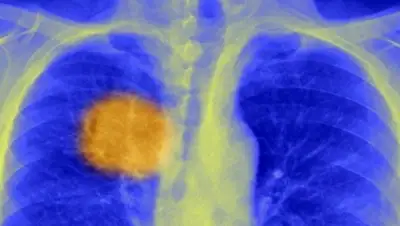

Британские ученые утверждают, что нашли способ заставить иммунную систему человека эффективно бороться с раковыми опухолями, сообщает Русская служба BBC.

Его суть заключается в том, чтобы найти самое уязвимое место каждой отдельно взятой опухоли – так сказать, ее Ахиллесову пяту – и нацелить на него иммунную систему.

О таком способе терапии говорили уже давно, но только сейчас, заявляют ученые из Университетского колледжа Лондона, им удалось найти механизмы для идентификации в структуре рака "слабых" участков.

Открытие подразумевает индивидуальный подход к каждому отдельному случаю заболевания раком, исследование клеток каждой опухоли, что на практике может стоить очень дорого. Однако на данный момент, говорят ученые, это самые обнадеживающие результаты в этой области за последние годы.

Дело в том, что раковая опухоль – это не единое, равномерное образование. Она состоит из совершенно разных, по-разному мутировавших клеток, поэтому и вести себя отдельные участки опухоли могут по-разному.

Раковую опухоль можно сравнить с деревом. У нее есть ствол, где началась мутация клеток, а потом от этого ствола в разные стороны разрастаются ветки, и в каждой проходят свои мутационные процессы.

Это называется гетерогенез.

Прорыв ученых заключается в то, что они научились распознавать клетки в стволе, которые изменяют антигены – белки, расположенные на поверхности опухолевых клеток.

Фото: SPL